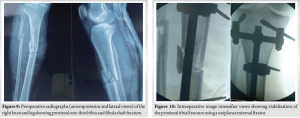

On the right side, the fractured 8th rib was reduced and stabilized with a 2 mm reconstruction plate. The wound was closed with a negative-pressure drain to prevent hematoma formation, which was removed after 48 h.Post-op X-ray (Fig. 7) shows well-aligned and reduced sternum with no evidence of pneumothorax or hemothorax.The open wound on the medial aspect of the proximal tibia (Fig. 8) was initially managed with urgent debridement, for the proximal tibia 1/3rd shaft fracture (Fig.-9) application of an external fixator (Fig. 10), and initiation of negative pressure wound therapy. After ensuring the wound was healthy, a flap coverage procedure was done by the plastic surgery team. Following flap maturation, the external fixator was removed, and the patient underwent closed reduction and internal fixation using tibial interlocking (intramedullary interlocking) nailing (Fig. 11).